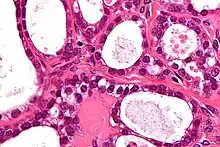

| High magnification micrograph of a Brenner tumor, a type of surface epithelial-stromal tumor. H&E stain. | |

Brenner tumor

Brenner tumors are uncommon surface-epithelial stromal cell tumors in which the epithelial cell (which defines these tumors) is a transitional cell. These are similar in appearance to bladder epithelia. The tumors may be very small to very large, and may be solid or cystic. Histologically, the tumor consists of nests of the aforementioned transitional cells within surrounding tissue that resembles normal ovary. Brenner tumors may be benign or malignant, depending on whether the tumor cells invade the surrounding tissue.